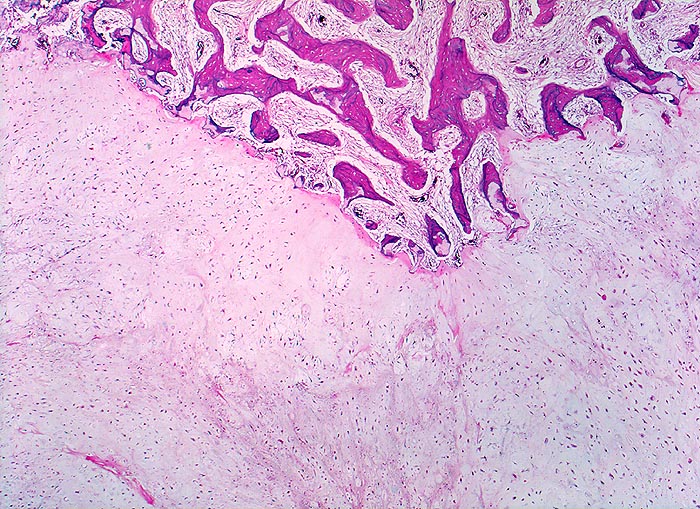

hoch differenziertes Chondrosarkom

maligner Tumor

Knochen, Rippe

Das Tumorgewebe (untere Bildhälfte) bildet reichlich helle chondroide Matrix. Die Zellularität im Tumor ist im Vergleich zu normalem Knorpel leicht erhöht und die Tumorzellen erscheinen etwas grösser als normale Chondrozyten. Das angrenzende Knochengewebe zeigt eine reaktive Markfibrose. An der Invasionsfront infiltriert und destruiert das Sarkom die Spongiosabälkchen.

Umschriebene Schmerzen im Bereich des Rippen-Thorax seit über einem Jahr.